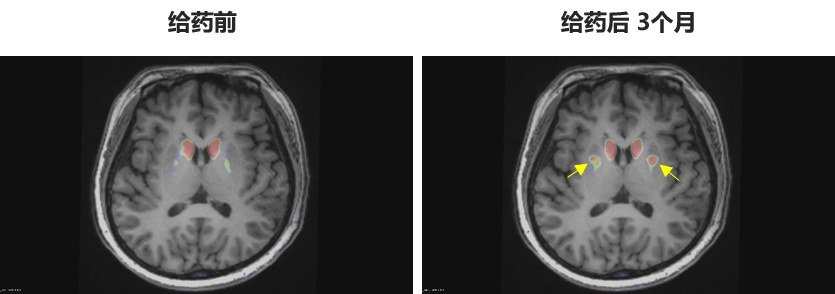

🔹多巴胺能功能成像:神经突触多巴胺能显像是评估人脑黑质纹状体神经元完整性和功能的“金标准”,常用于帕金森病亚临床诊断1-2。接受移植手术3个月后PET-DAT/MRI融合影像明确显示,移植细胞已在患者脑内定植并成功转化为有功能的多巴胺能神经元,双侧纹状体形成显著的de novo新生多巴胺能活性成像(如下图箭头所指), 为功能性治愈提供了最直观的证据。

EOPD患者PET-DAT/MRI融合图像术前与术后三个月对比

注:影像图中黄色箭头指示为NCR201移植后,双侧纹状体出现的新生多巴胺能活性信号,提示移植细胞已定植并高效转化为功能性多巴胺能神经元